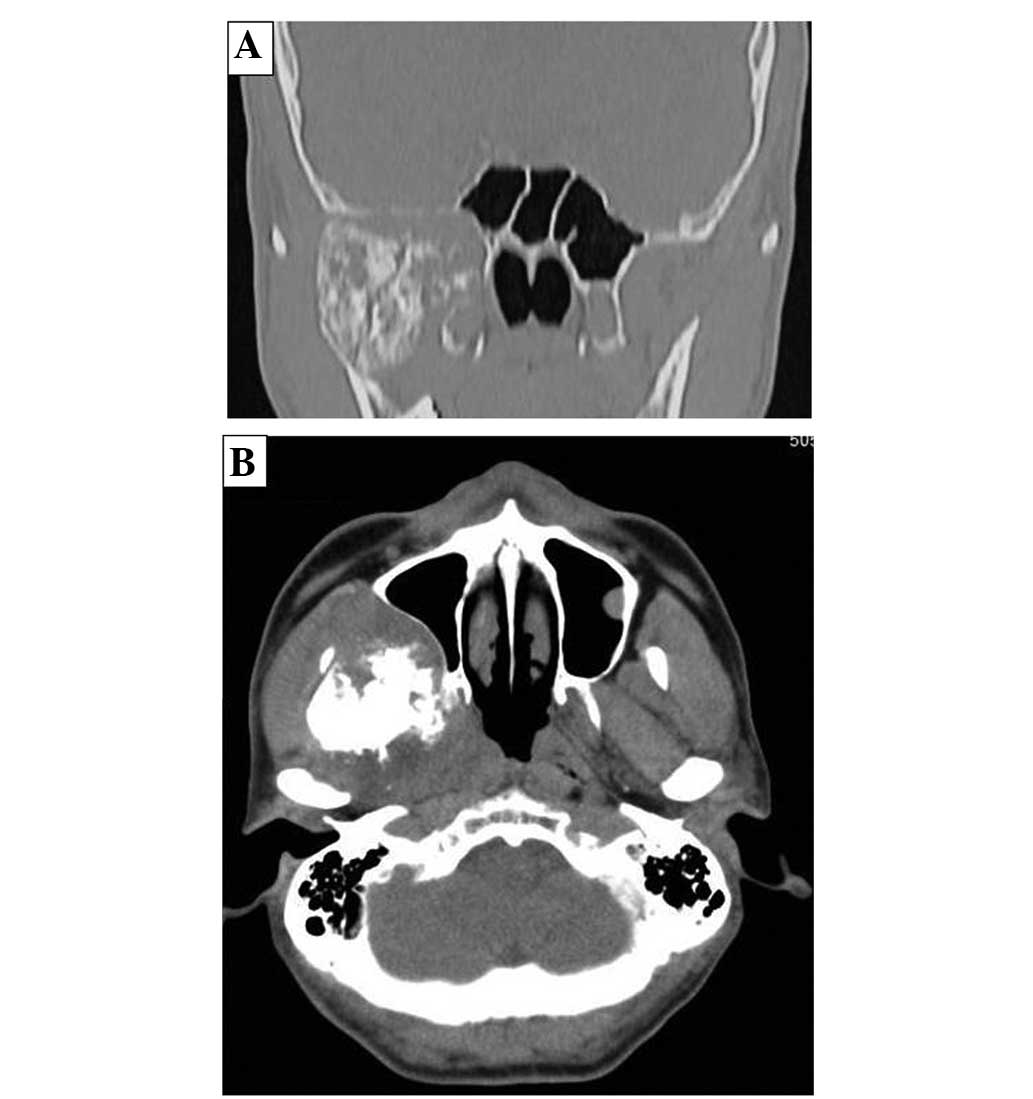

Figure 1

(A) Coronal and (B) axial view of regional computed tomography showing the mass with prominent ossification in the right parapharyngeal space.

A 56-year-old male presented with a mass in the right facial bone that had been apparent for three months, and dysesthesia, which had occurred gradually at this site. The patient incidentally identified the tumor and visited Wakakusa-Daiichi Hospital, Higashi-Osaka (Osaka, Japan), where the mass was confirmed with computed tomography (CT) examination. Nothing of note was found in the patient’s past medical and family histories, and the findings from the routine laboratory studies were within the normal limits. Plain X-rays showed no particular findings, but regional CT showed a soft-tissue mass with prominent ossification in the central region, and involving the parapharyngeal space (Fig. 1), in which the anterior septum ballooned owing to compression from the mass. Magnetic resonance imaging (MRI) revealed heterogeneously low intensity to isointensity results on T1-weighted sequences and low to moderately high intensity results on T2-weighted images, with a size of 5.6×4.8 cm (Fig. 2). Lung CT revealed multiple small nodules that were suspected to be lung metastases (Fig. 3).

Radiologically, tumor matrix mineralization and aggressive bone destruction are strongly suggestive of osteosarcoma. The present case demonstrated a high-density mass in the central area of the tumor on CT examination. On MRI, an intermediate intensity region was observed T1-weighted images and a heterogeneously high intensity region was observed on T2-weighted images. An ossified region in the central lesion, which was produced by tumor cells, showed a low intensity on each of the T1- and T2-weighted images. There was no discernible bone-forming reaction to indicate an osteosarcoma (7).